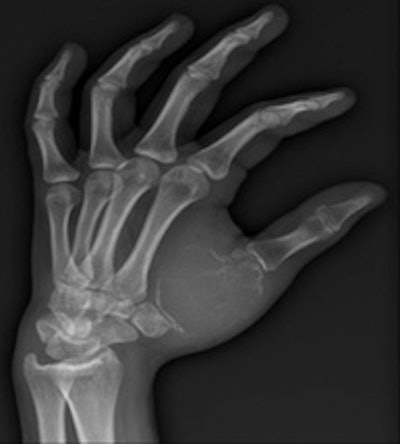

Bilbao and his colleagues are shown in the angiography suite at Clínica Universidad de Navarra.How are Spain's well-documented economic difficulties affecting you?